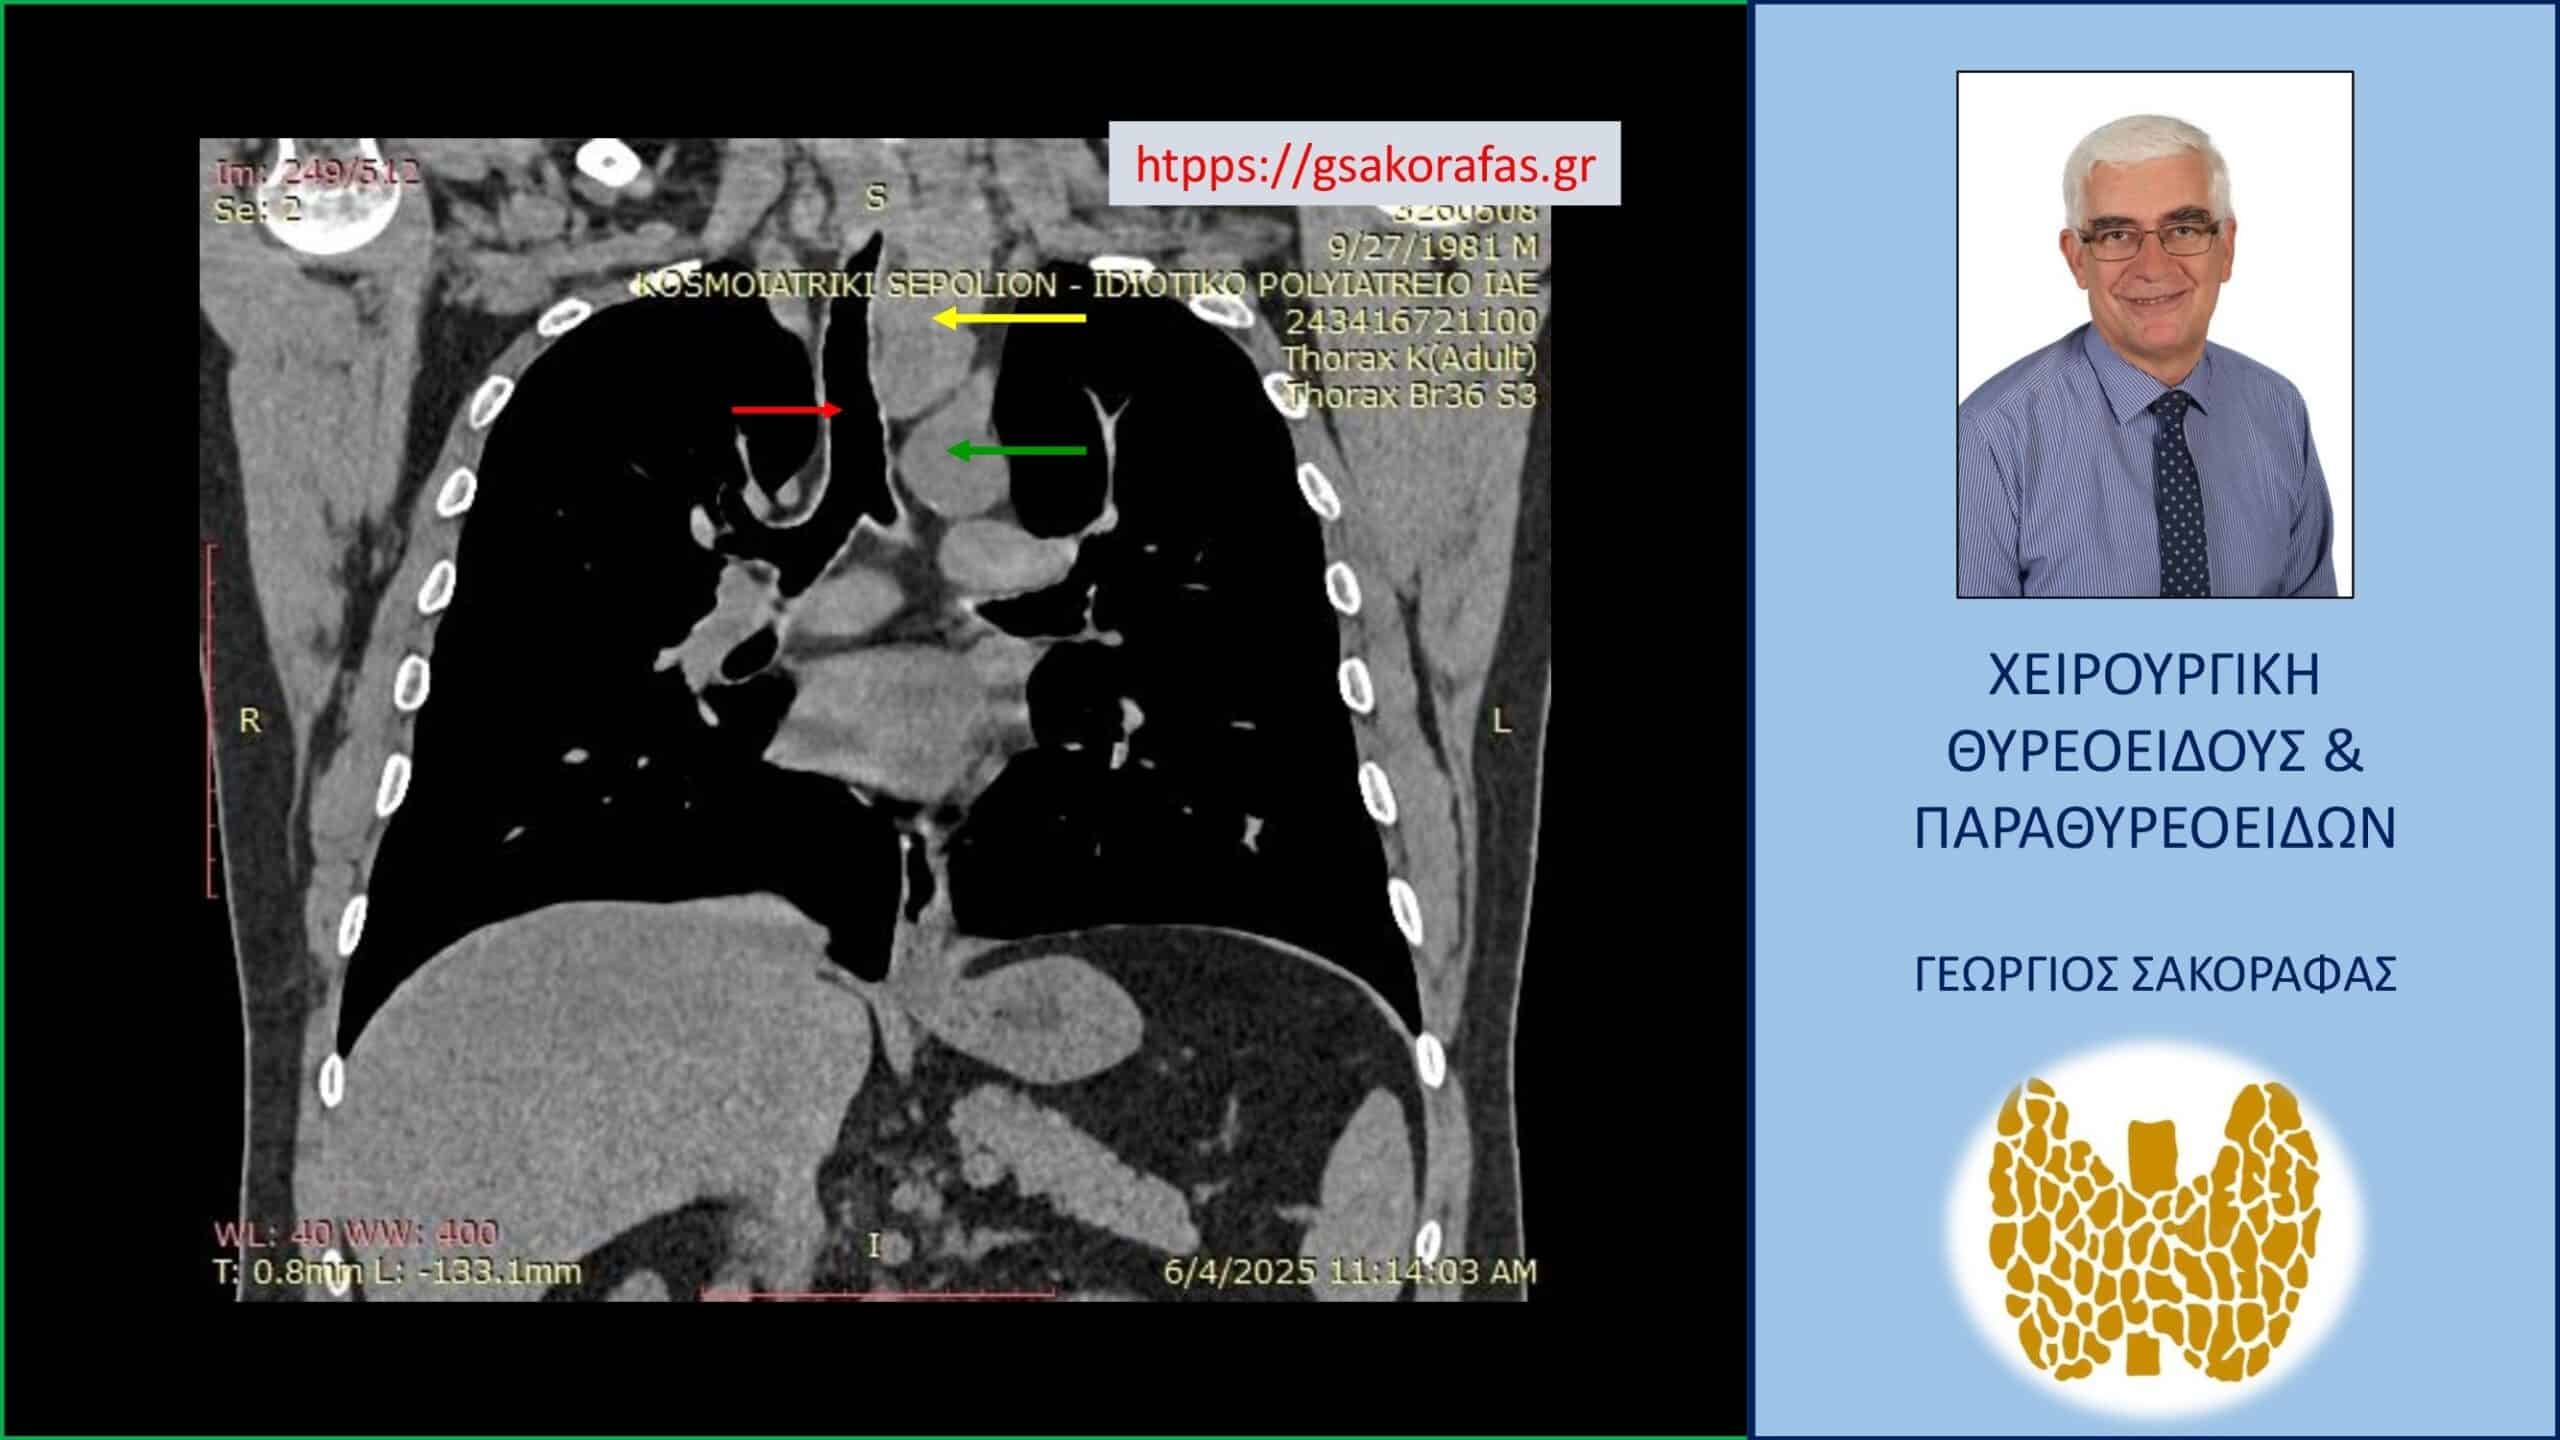

Αξονική τομογραφία – απεικόνιση σε κατά μέτωπο διατομή. Εμφανής η μεγάλου βαθμού διόγκωση και η κατάδυση σε βάθος του αριστερού λοβού (κίτρινο βέλος), που φθάνει στις παρυφές του αορτικού τόξου (πράσινο βέλος), με την τραχεία (κόκκινο βέλος) να απωθείται προς τα δεξιά από τον διογκωμένο αριστερό λοβό.

Καταδυόμενη βρογχοκήλη με κατάδυση σε βάθος στο θώρακα – εικόνα στην αξονική τομογραφία (κατά μέτωπο διατομή, σε άλλο επίπεδο). Εμφανής η μεγάλου βαθμού διόγκωση και η κατάδυση σε βάθος του αριστερού λοβού (κίτρινο βέλος), που φθάνει στις παρυφές του αορτικού τόξου (πράσινο βέλος), με την τραχεία (κόκκινο βέλος) να απωθείται προς τα δεξιά από τον διογκωμένο αριστερό λοβό. Ο καταδυόμενος αριστερός λοβός φθάνει σε βάθος λίγο πιο πάνω από τον διχασμό της τραχείας στους δύο στελεχιαίους βρόγχους.